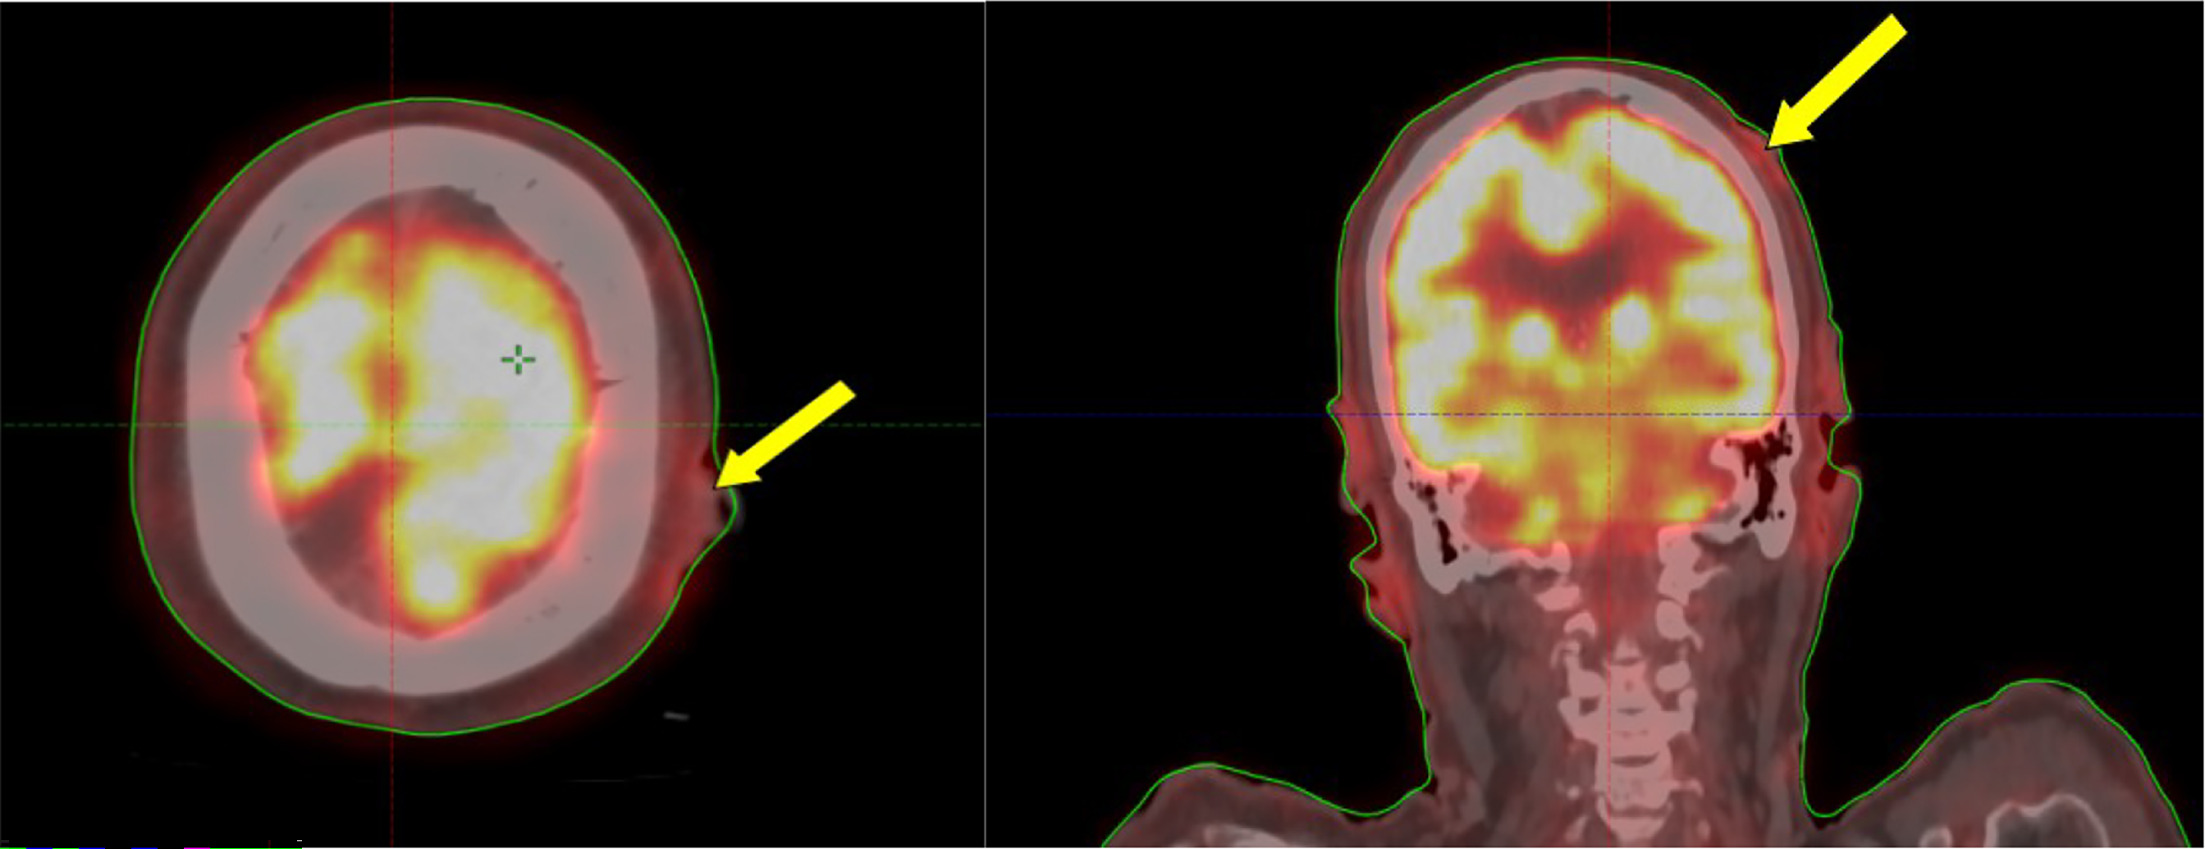

Electron-Beam Treatment Planning Process

Simulation using computed tomography (CT) was performed with the patient immobilized in the supine treatment position using a thermoplastic mask. Target volume was contoured (on the planning CT images), which included the gross scalp lesion visible on clinical examination (Figure 1A), planning CT scan, and positron emission tomography/CT (PET/CT) (Figure 2). A 2-cm uniform circumferential clinical target volume (CTV) margin was given to include the possible microscopic extension of the disease in the adjacent surrounding tissue. A 5-mm planning target volume (PTV) margin was given from the CTV to create the final target volume. Treatment planning was done on the Varian Eclipse treatment planning system using a 6-MeV nonisocentric electron beam and a gantry angle of 90° and collimator angle of 0°, with a 5-mm wet cotton bolus covering the PTV. The patient received 30 Gy in 15 fractions, 2 Gy per fraction, 5 days a week over 3 weeks. Figure 3 shows the radiation dose coverage of the target volume. Here, 99% of the gross tumor volume (GTV) and CTV received 95% of the prescribed dose. Also, 94% of the PTV received 85% of the prescribed dose (Figure 4). The patient tolerated the treatment well without any significant side effects. At the end of the treatment, the patient had grade 2 skin reactions (grading based on RTOG [Radiation Therapy Oncology Group] acute radiation morbidity) that subsided over 2 weeks.

Imaging Findings

Whole-body PET/CT (Figure 2) showed a cutaneous lesion on the left parietal scalp measuring 25 × 7-mm, with a mild 18-fluorodeoxyglucose (FDG) standardized uptake value (SUV)max of 3.5. No other skin lesions were seen, and there was no evidence of any significant lymph nodal or other organ involvement.